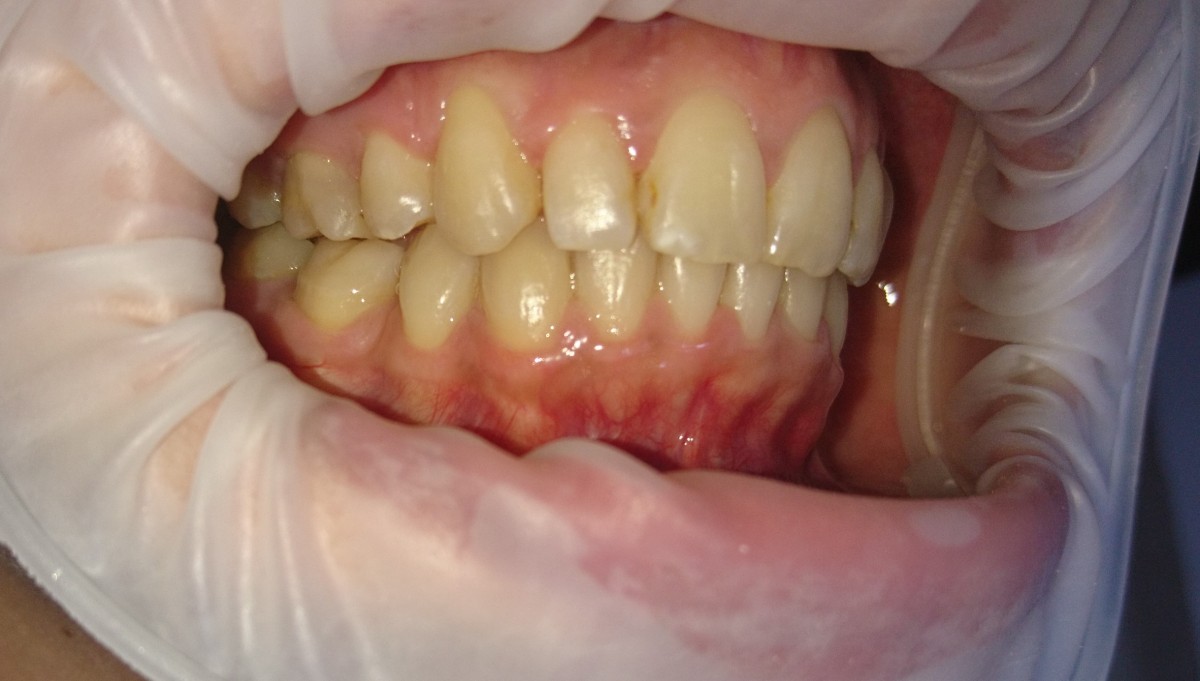

Pacient 23 ani. Extracție 1.4, 2.4, 3.5, 4.5, aparat ortodontic fix ceramic.